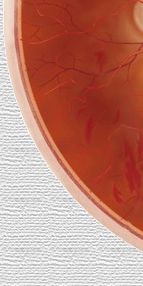

Mácula |

Nervio

óptico |

Retina |

Esclerótida

|

Coroides |